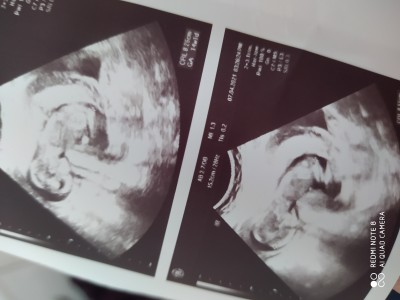

Arkadaşlar 14+2,3 günlük gebelik bugün hastaneden geldim doktor cinsiyet tahmini yaptı ama arkası dönük net bir şey göremiyorum boşluk kıza benziyor gibi dedi ama daha erken dedi organları net tmamalanmıyo daha bu haftada dedi sizce neye benziyor siz doktorun dediğinden ne çıkardınız zaten bir baktı arkası dönük bacakları kapalı

dedi 2,3 haftaya netleşwbilşr dedi